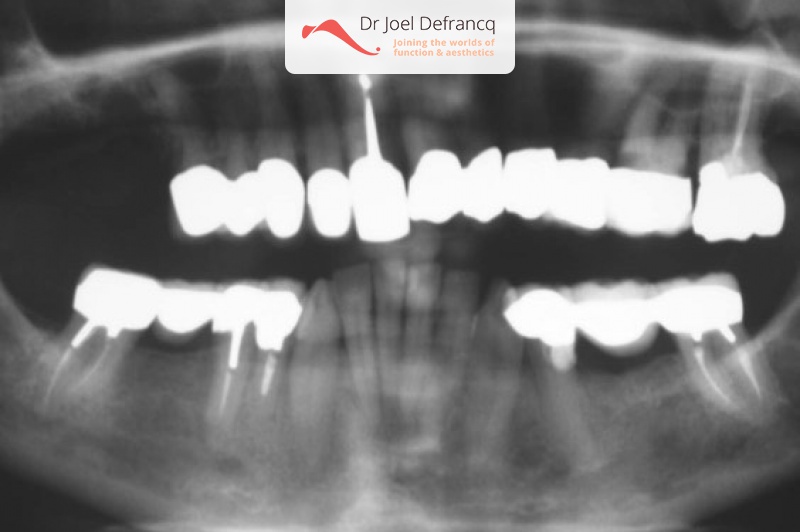

Dentale diagnose

- Klasse I

Behandeling tandheelkundige implantaten

- Vaste tanden op implantaten (bovenkaak)

- Vaste tanden op implantaten (onderkaak)